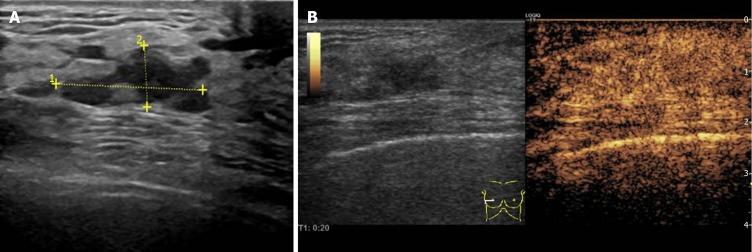

Breast non-mass-like lesions (NMLs) account for 9.2% of all breast lesions. The specificity of the ultrasound diagnosis of NMLs is low, and it cannot be objectively classified according to the 5 Edition of the Breast Imaging Reporting and Data System (BI-RADS). Contrast-enhanced ultrasound (CEUS) can help to differentiate and classify breast lesions but there are few studies on NMLs alone.

To analyze the features of benign and malignant breast NMLs in grayscale ultrasonography (US), color Doppler flow imaging (CDFI) and CEUS, and to explore the efficacy of the combined diagnosis of NMLs and the effect of CEUS on the BI-RADS classification of NMLs.

A total of 51 breast NMLs verified by pathology were analyzed in our hospital from January 2017 to April 2019. All lesions were examined by US, CDFI and CEUS, and their features from those examinations were analyzed. With pathology as the gold standard, binary logic regression was used to analyze the independent risk factors for malignant breast NMLs, and a regression equation was established to calculate the efficiency of combined diagnosis. Based on the regression equation, the combined diagnostic efficiency of US combined with CEUS (US + CEUS) was determined. The initial BI-RADS-US classification of NMLs was adjusted according to the independent risk factors identified by CEUS, and the diagnostic efficiency of CEUS combined with BI-RADS (CEUS + BI-RADS) was calculated based on the results. ROC curves were drawn to compare the diagnostic values of the three methods, including US, US + CEUS, and CEUS + BI-RADS, for benign and malignant NMLs.

Microcalcification, enhancement time, enhancement intensity, lesion scope, and peripheral blood vessels were significantly different between benign and malignant NMLs. Among these features, microcalcification, higher enhancement, and lesion scope were identified as independent risk factors for malignant breast NMLs. When US, US + CEUS, and CEUS + BI-RADS were used to identify the benign and malignant breast NMLs, their sensitivity rates were 82.6%, 91.3%, and 87.0%, respectively; their specificity rates were 71.4%, 89.2%, and 92.9%, respectively; their positive predictive values were 70.4%, 87.5%, and 90.9%, respectively; their negative predictive values were 83.3%, 92.6%, and 89.7%, respectively; their accuracy rates were 76.5%, 90.2%, and 90.2%, respectively; and their corresponding areas under ROC curves were 0.752, 0.877 and 0.903, respectively. tests showed that the area under the ROC curve of US was statistically smaller than that of US + CEUS and CEUS + BI-RADS, and there was no statistical difference between US + CEUS and CEUS + BI-RADS.

US combined with CEUS can improve diagnostic efficiency for NMLs. The adjustment of the BI-RADS classification according to the features of contrast-enhanced US of NMLs enables the diagnostic results to be simple and intuitive, facilitates the management of NMLs, and effectively reduces the incidence of unnecessary biopsy.